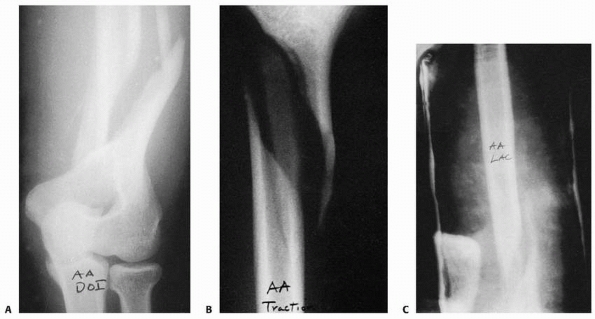

characterize fractures of the medial third of the clavicle and

sternoclavicular injuries. The “serendipity” view, where a broad x-ray

beam with 40 degrees of cephalic tilt projects both clavicles on the

same film, is helpful for evaluating fractures in this portion of the

clavicle (Fig. 17-3).459

By comparing with the uninjured contralateral side, the location of

injury and the degree of displacement often can be determined. However,

this view can be difficult to interpret, especially for mild injuries.

Currently, CT is the best method for evaluating injuries in the medial

third of the clavicle. Thin slice CT provides detailed information

about the morphology of the medial clavicle, the medial physis, the

degree of displacement, and possible injury to the underlying

intrathoracic structures (Fig. 17-4). Virtually

every acute injury of the medial end of the clavicle should be

evaluated with CT, and it also is useful for follow-up of chronic

injuries.